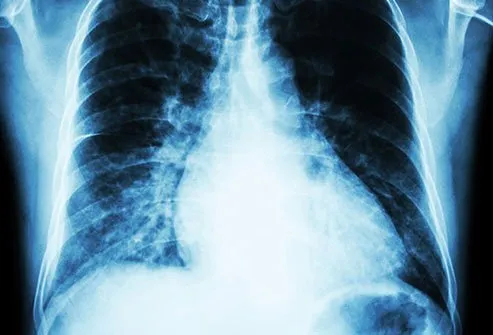

بزرگ شدن قلب

همچنان که قلب شما سختتر کار می کند تا خون را به اندامهای شما برساند، ماهیچه قلب شما ضخیم می شود. در نتیجه کل قلب شما بزرگتر می شود. هر چه قلب شما بزرگتر شود، توانایی کمتری در انجام کار خود دارد، به این معنی که بافت های شما ممکن است اکسیژن و مواد مغذی مورد نیاز خود را دریافت نکنند.